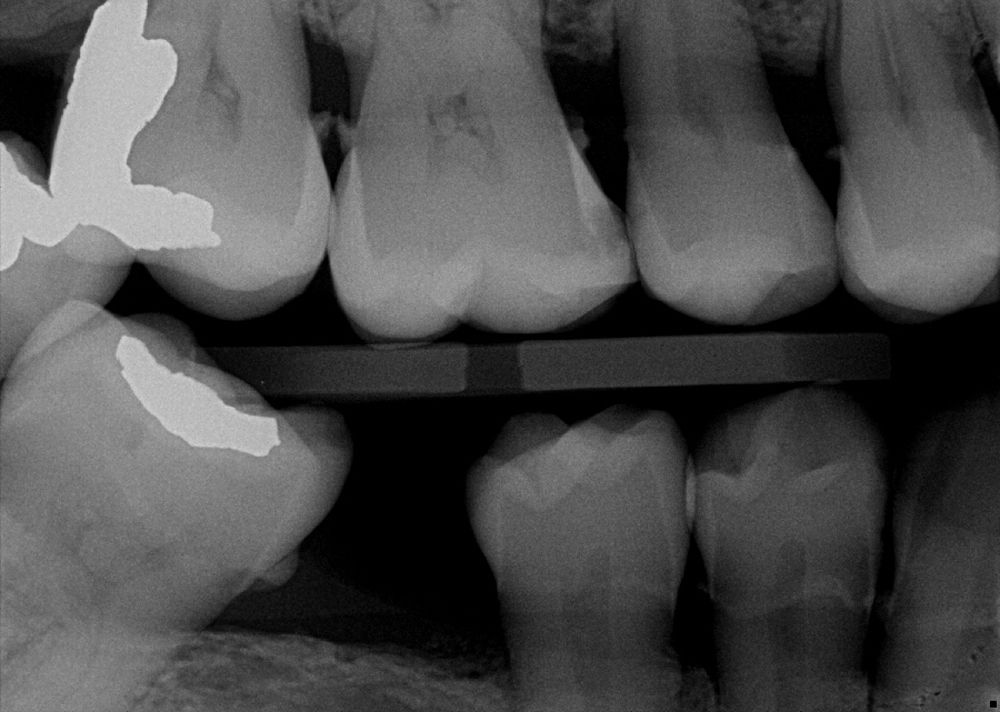

The AI technology analyzes and annotates x-rays in real time, adding a layer of data to the radiographs (this image is without AI) to help with clinical decision-making and patient education.